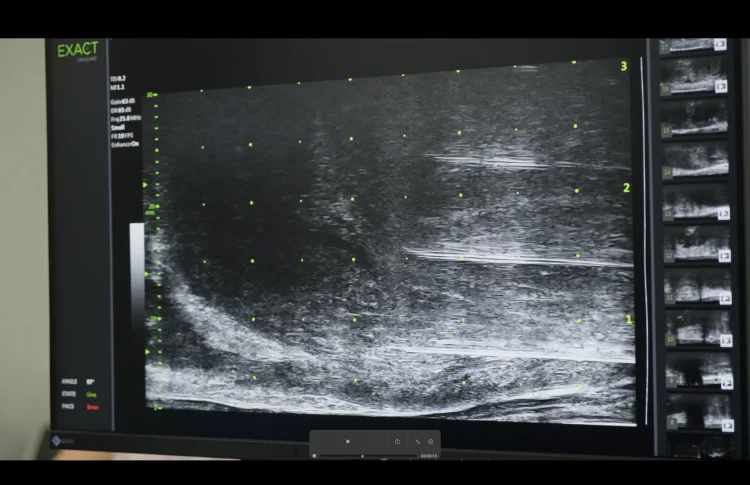

Its operation is based on high-frequency ultrasound, providing up to 300% improved imaging compared to conventional ultrasound. Thanks to real-time “live” visualization, identification of suspicious areas, and its application for targeted transperineal or transrectal biopsy, micro-ultrasound has no equal worldwide.

Transperineal and transrectal targeted prostate biopsies are considered minor urological procedures. During the process, a special probe is inserted into the rectum to visualize the prostate. Suspicious areas are identified and biopsied.

Micro-ultrasound-guided prostate biopsy effectively identifies suspicious areas for prostate cancer and allows for 100% accurate targeting of tissue sampling. Its effectiveness is supported by numerous scientific studies.